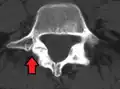

Anterolisthesis L5/S1

Isthmic anterolisthesis is where there is a defect in the pars interarticularis.[12] It is the most common form of spondylolisthesis; also called spondylolytic spondylolisthesis, it occurs with a reported prevalence of 5–7 percent in the US population. A slip or fracture of the intravertebral joint is usually acquired between the ages of 6 and 16 years, but remains unnoticed until adulthood. Roughly 90 percent of these isthmic slips are low-grade (less than 50 percent slip) and 10 percent are high-grade (greater than 50 percent slip).[9] It is divided into three subtypes:[13]

- Isthmic anterolisthesis (a.k.a. type 2) is caused by a defect in the pars interarticularis but it can also be seen with an elongated pars.